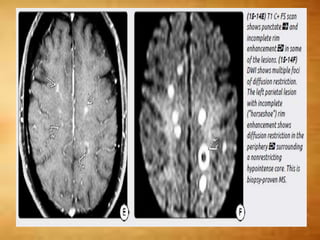

T1 C+

 Active demyelination - transient enhancement

- Punctate, nodular, linear, and rim patterns are

seen

 Large tumefactive lesions – horseshoe

enhancement- open nonenhancing segment

facing the cortex

DWI

• Majority of acute plaques - normal or increased

diffusivity.

• Occasionally acute MS plaques can demonstrate

restriction on DWI - atypical - should not be

considered a reliable biomarker of plaque activity